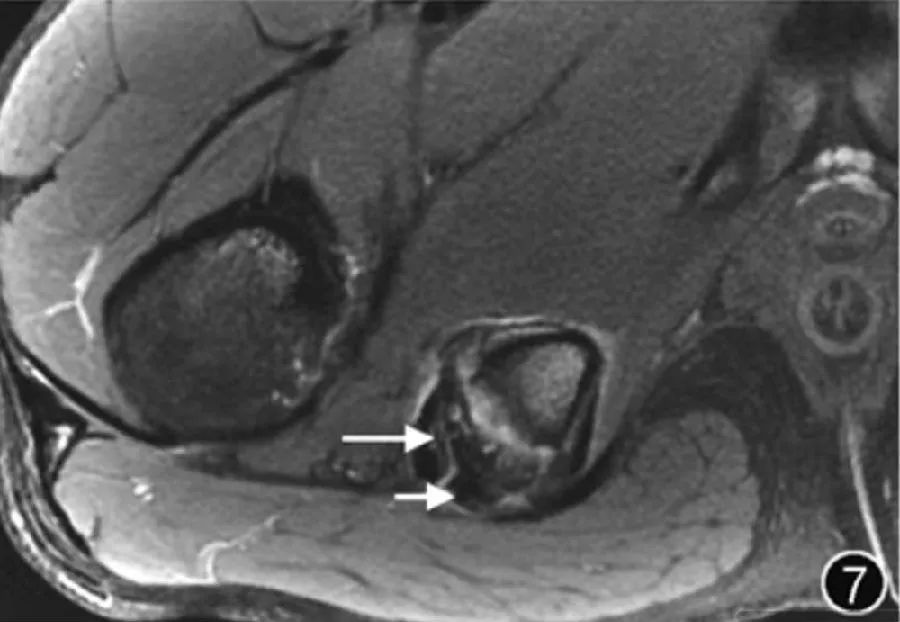

6.Травмы мышц и сухожилий: на растяжения мышц приходится значительная часть всех острых спортивных травм. Сухожилия малой и средней ягодичных мышц чаще всего повреждаются в месте прикрепления тазобедренного сустава, а частичные разрывы встречаются чаще, чем в месте прикрепления. точка вставки встречается чаще. МРТ рекомендуется для лучшего понимания местоположения и степени поражения, прогнозирования времени восстановления, клинических исходов и другой соответствующей информации. В прошлом острые мышечные травмы обычно делили на растяжения (степень I), частичные разрывы (степень II) и полные разрывы (степень III). Хотя в настоящее время существует множество систем классификации и классификации мышечных травм, таких как классификация BAMIC, которые можно использовать для классификации травм, ценность их клинического применения еще предстоит уточнить (рис. 7).

Рисунок 7. МРТ-изображение травмы сухожилия подколенного сухожилия.

На поперечном срезе Т2-ВИ на уровне седалищного бугорка можно наблюдать как сухожилие полуперепончатой мышцы (длинное ↑), идущее в передне-латеральном направлении, так и комбинированное сухожилие двуглавой мышцы бедра и полусухожильной мышцы (короткое ↑), идущее латеральнее седалищного бугорка. Утолщение с высоким сигналом.